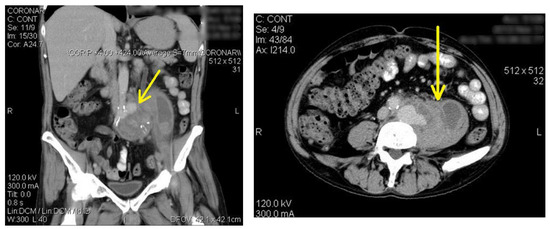

Introduction: The risk of secondary endovascular infections after bacteremia with Salmonella spp. is augmented by preexisting atherosclerotic arterial lesions. Over the age of 50, the incidence varies between 25 and 35%. Case report: A 57‐year‐old ma...